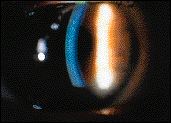

Over the past decade, researchers have begun to suspect that hypoxic corneal swelling is only part of a more complex picture. Corneal edema is a sentinel sign of hypoxic distress, however, this does little to explain the increased rate of complications associated with extended wear (Fig. 1). Much research has been directed at finding the "missing-link" between hypoxia and clinical complications. To date, no definitive findings have been found.

FIG. 1: Epithelial edema.